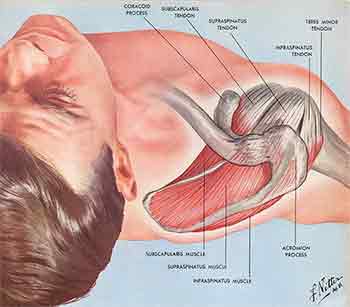

It has been my experience that non-surgical Shoulder joint problems such as frozen shoulder, glenoid capsulitis, rotator cuff injury and Biceps tendinitis syndromes are very common and are extremely amenable to a mobilization approach. They range from the acute, sudden swelling of a bursa/joint to long standing cases of frozen shoulder.

Predisposing factors: Muscle 'tethering' by the Pectoralis minor, Subscapularis, Supraspinatus, Infraspinatus and the Teres group. The deep fibres of Biceps are usually involved as well. These tight muscles effectively 'hold' the head of the Humerus too far forwards in the socket and at the same time 'tether' the Humerus such that it cannot be lifted to its full potential range.